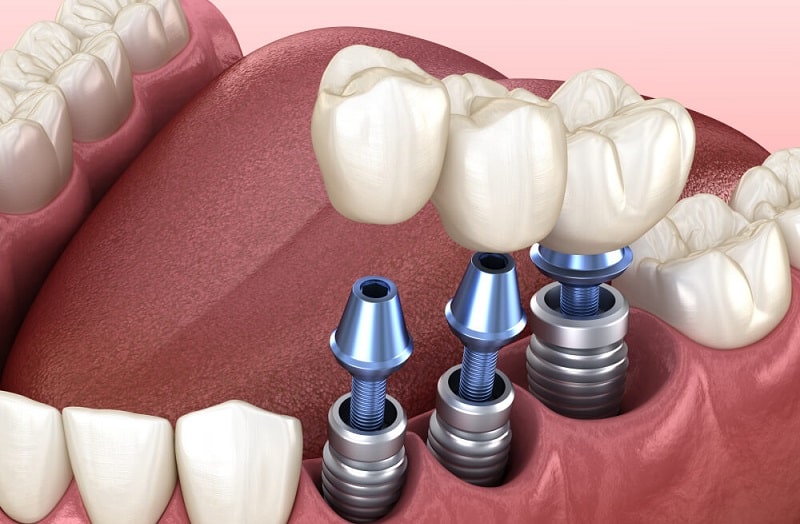

در این روش، یک پایه تیتانیومی که با استخوان فک سازگار است، در داخل استخوان فک کاشته میشود.

این پایه مانند ریشه دندان طبیعی عمل کرده و پس از جوش خوردن با استخوان، یک روکش دندان مصنوعی روی آن قرار میگیرد.

۲. جراحی کاشت پایه تیتانیومی

پس از آمادهسازی بیمار، جراحی برای کاشت پایه ایمپلنت انجام میشود. مراحل این جراحی شامل موارد زیر است:

- بیحسی موضعی یا در برخی موارد آرامبخشی برای کاهش استرس بیمار

- ایجاد برش در لثه و کنار زدن آن برای دسترسی به استخوان فک

- ایجاد سوراخی در استخوان فک و قرار دادن پایه تیتانیومی (که بهعنوان ریشه مصنوعی عمل میکند)

- بخیه زدن لثه و قرار دادن یک محافظ روی محل جراحی برای جلوگیری از عفونت

این مرحله بسته به پیچیدگی شرایط بیمار، بین ۳۰ تا ۹۰ دقیقه طول میکشد.

۴. قرار دادن اباتمنت (اتصالدهنده)

پس از جوش خوردن پایه ایمپلنت با استخوان فک، مرحله بعدی قرار دادن اباتمنت است.

این قطعه مانند یک رابط بین پایه ایمپلنت و تاج دندان مصنوعی عمل میکند. برای این کار:

- لثه در ناحیه ایمپلنت باز شده و اباتمنت روی پایه قرار میگیرد.

- معمولاً ۲ هفته زمان نیاز است تا لثه اطراف اباتمنت ترمیم شود.

- در برخی موارد، اباتمنت همزمان با کاشت پایه نصب میشود تا نیاز به جراحی دوم نباشد.

۵. نصب روکش نهایی

مرحله نهایی شامل ساخت و نصب تاج دندان است.

این روکش از جنس سرامیک، زیرکونیا یا مواد دیگر ساخته میشود تا ظاهری طبیعی و مقاوم داشته باشد.

- ابتدا از دندانهای بیمار قالبگیری میشود تا روکش کاملاً متناسب با شکل و رنگ سایر دندانها باشد.

- پس از آماده شدن روکش، آن را روی اباتمنت قرار داده و تنظیمات نهایی انجام میشود.

پس از نصب روکش، بیمار میتواند مانند دندان طبیعی از ایمپلنت استفاده کند.